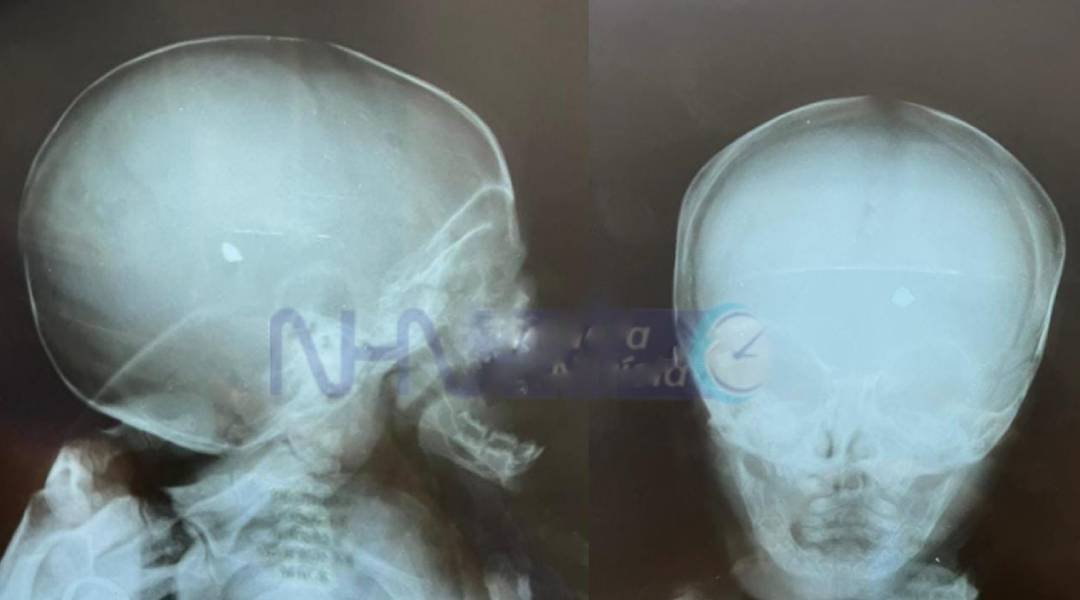

O bebê do sexo masculino de apenas 02 meses de vida, que no final da tarde da última quarta-feira, 04, no Conjunto Habitacional Cidade do Povo, foi alvejado com um tiro de revólver e ficou com um projétil alojado na cabeça, continua internado na Unidade de Tratamento Intensivo – UTI em estado grave.

O recém-nascido não foi submetido a cirurgia, porque a equipe médica avaliou a impossibilidade de retirada do objeto estranho de dentro da cabeça do bebê.